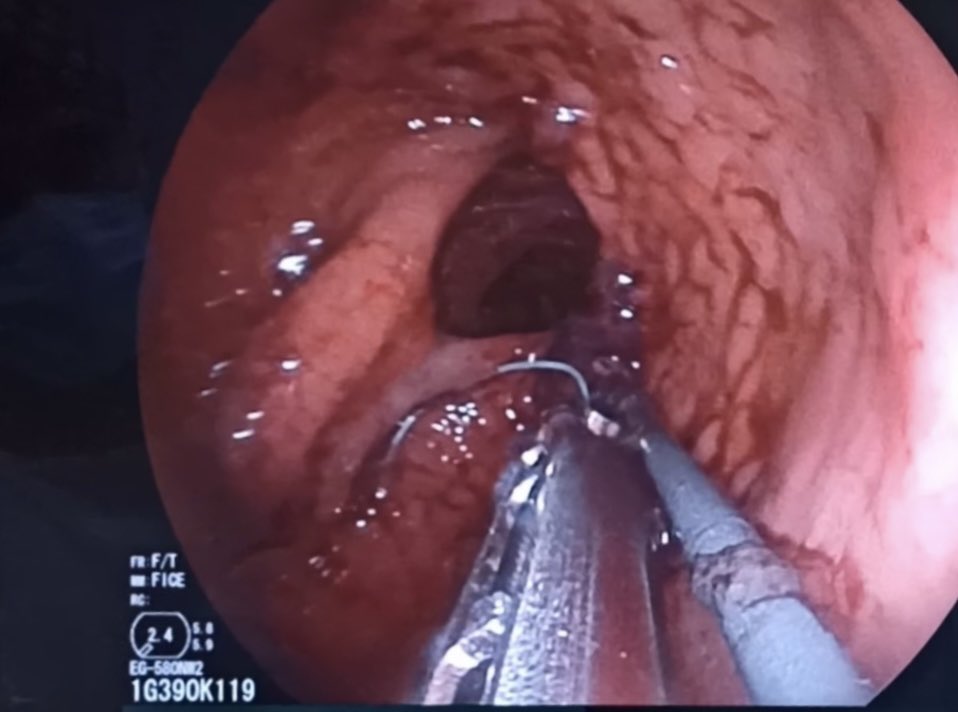

#MedCase 🧓 65 años con ingesta accidental de cuerpo extraño hace 24 horas. Intento fallido de extracción es referida para tratamiento. Endoscopia asistida por cap. Retiro con campaña “artesanal” de Hood. Se observa laceración esofágica y colocación de clips.